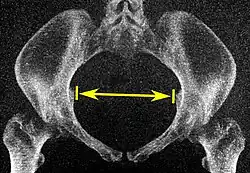

Low-dose 3D-rendered CT scans can be used for estimating the main pelvimetry parameters:[4]

Parameter Maximum intensity projections[5] Thin slices End points Normal measures

Pelvic inlet Transverse diameter of the pelvic inlet

Coronal plane

The iliopectineal lines, at widest transverse distance. 13 to 14.5 cm.[4]